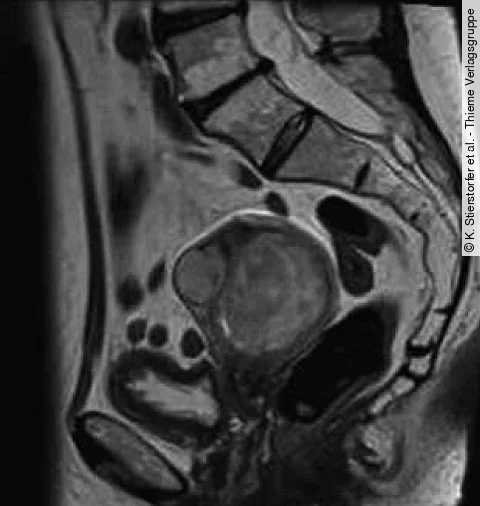

Eine 38-jährige Frau ist nach spontaner Empfängnis schwanger mit monochorioten, diamnioten Zwillingen. Ihre Krankengeschichte umfasst eine Wirbelsäulenentzündung und Tagesschläfrigkeit.